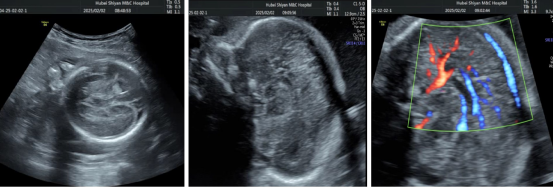

胎儿系统超声检查

俗称"大排畸“检查,对胎儿进行全面系统的结构筛查,能诊断出是否存在严重的结构畸形,从而降低严重缺陷儿出生。

胎儿超声心动图

是超声医学科的名片,是金牌强项,是开展时间最早、诊断疑难病例最多的亚专业,承担来着市内外的疑难复杂病例的超声会诊工作。在多切面联合扫查的基础上运用三节段分析法,将胎儿心脏多个切面有序联合,可以快速判断胎儿心脏是否正常,精确诊断胎儿心脏畸形。

胎儿产前多普勒技术

胎儿多普勒超声可以准确评价胎儿血流动力学,胎儿出现宫内窘迫时,其血流动力学指标会出现明显变化,应用产前多普勒技术可明显改善妊娠结局。